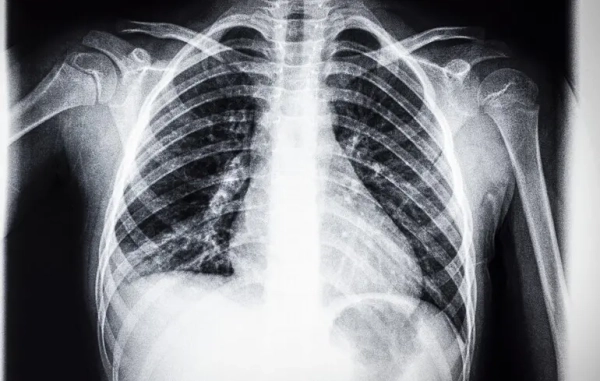

© Getty Images Австралійські вчені розробили для цього спеціальну програму машинного навчання.

Національне наукове агентство Австралії CSIRO першим у світі розробило програму машинного навчання, щоб спеціалізувати штучний інтелект на читанні рентгену грудної клітини. Натренований у такий спосіб ШІ виявився дуже корисним при діагностиці, повідомляє Medical Xpress.

Для спеціалізації ШІ на читанні рентгенів медичні інженери CSIRO створили базу даних із 46 000 анамнезів реальних пацієнтів, наданих лікарнями США. Також у велику мовну модель завантажили інформацію про всі існуючі стандарти та вимоги до читання радіологічних звітів.

Перевірка на практиці показала, що штучний інтелект на 17% краще ставить діагнози пацієнтам, ніж це робили професійні рентгенологи. Професія зараз переживає у всьому світі нестачу кадрів, тож технологія може вирішити цю проблему і допомогти покращити роботу багатьом медичним закладам.

Це не вперше ШІ використовують для читання рентгенівських знімків. Але австралійська програма дає можливість навчити штучний інтелект повноцінно використовувати анамнез пацієнтів, а не лише плівку.

“Штучний інтелект функціонує як діагностичний детектив, а ми оснащуємо його додатковими доказами. Коли ви поєднуєте те, що видно на рентгенівському знімку, з даним про пацієнта, штучний інтелект стає точнішим і набагато кориснішим.